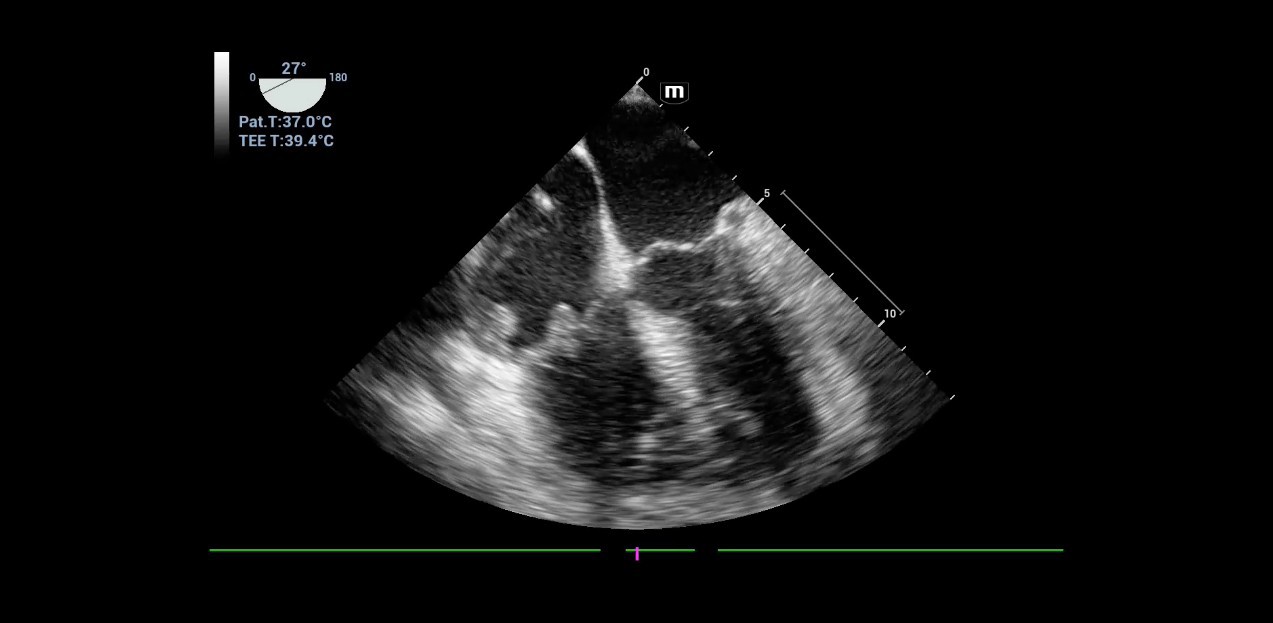

Bestens geeignet sei die Ger?tetechnik auch zur DurchfÞhrung einer trans?sophagealen Echokardiographie (TEE), auch als Schluckecho bekannt. Dabei findet die kardiale Bildgebung Þber eine Ultraschallsonde statt, die in die Speiser?hre eingefÞhrt und bis hinter das Herz geschoben wird. Im intensivmedizinischen Setting nimmt diese Verfahrensweise einen besonderen Stellenwert ein. Denn h?ufig ist ein normaler Herzultraschall gerade bei beatmeten Patienten aus praktischen GrÞnden kaum oder gar nicht m?glich, weil sie fÞr die Untersuchung u. a. nicht optimal positioniert werden k?nnen.